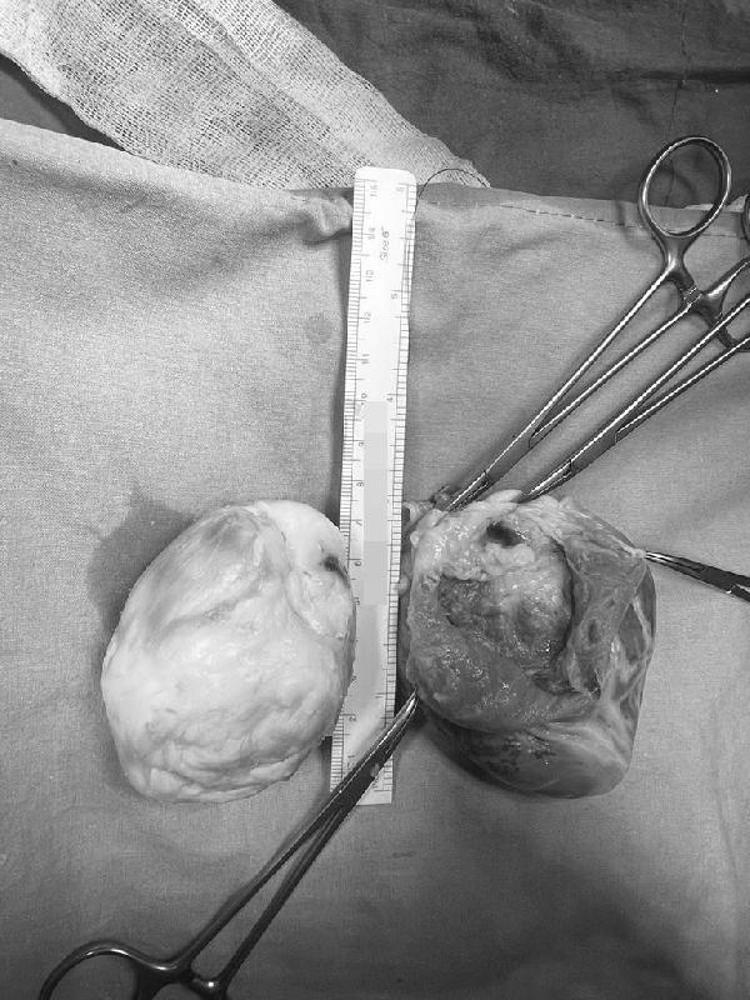

“Bu çocuğun ben ikinci doğumuna tanık oldum" diyen Koç Üniversitesi Tıp Fakültesi Hastanesi Pediatrik ve Konjenital Kalp ve Damar Cerrahisi Bölüm Başkanı Prof. Dr. Afksendiyos Kalangos, sözlerini şöyle sürdürdü: “Ekin Ada kızımızla 32 haftada anne karnındayken ilk olarak tanıştım. Fetal EKO'sunda bir kalp tümörü tespit edilmişti. Kızımız doğdu, ondan sonra 3 ila 6 aylık aralarla izlemeye başladık. Kalp içindeki tümör yaşı büyüdükçe, kalple beraber büyüyordu. Bu tümörlerin bir kötü tarafı da ritim düzensizlikleri yaratmaları. Ani ölüm riskinin çok yüksek olduğu vakalar bunlar. Tümörün büyüklüğü neredeyse kalp kadar olmuştu. 7 santimlik bir tümör, Ekin Ada'nın kalbi 8 santim uzunluğundaydı zaten. Sol karıncıktaki tümörün bir büyük tehlikesi daha vardı. Önemli bir koroner arter damar, tümörün içinden geçiyordu."

Tümörün içinden hayati bir damarın geçmesi nedeniyle kalp yerindeyken ameliyat etmenin imkansız olduğunu anlatan Prof. Dr. Kalangos, çok büyük bir riske girerek kalbi yerinden çıkarıp ameliyat etme yolunu seçtiklerini vurguladı. Prof. Dr. Kalangos, “Çok dikkatli çalışmamız gerekiyordu o nedenle kalbi yerinden söktük, damarlarından ayırdık ve masanın üzerine yatırarak (kalp vücuttan ayrıyken) ameliyata devam ettik. Göğüs boşluğu tamamıyla boş kaldı, 'kalpsiz' bir durumda makineye bağlı takip edildi. Kalbi masanın üzerinde sol karıncığa hasar vermeden, hem kasları hem arterleri koruyarak açtık. Dr. Yılmaz Zorman ile beraber nefesimizi tuttuk, ince ince, soğan kabuğu soyar gibi kalp kasından tümörü ayırdık. Tümörün içinden geçen o ince, bir milimetrelik koroner damarı bulduk ve onu da titiz bir şekilde tümörden ayırarak kalbi tamamen temizledik. Onarılmış kalbi tekrar yerine taktık" dedi.